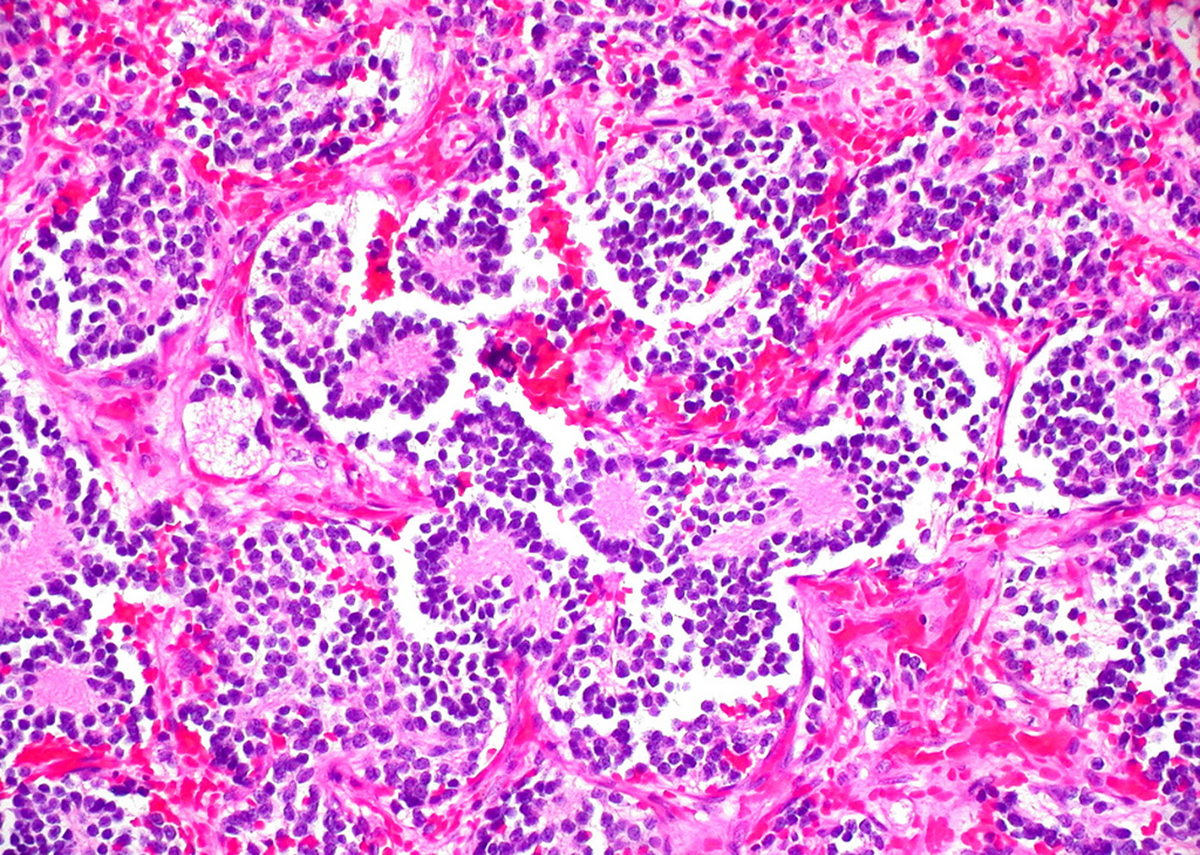

This type of cancer originates in the neuroblasts, which are immature nerve cells. The cells are made by the growing fetus. Most neuroblasts develop into nerve cells by the time a baby is born. But in some cases, a few neuroblasts are still present in infants. Eventually, those cells also mature into nerve cells. In instances of neuroblastoma, the neuroblasts become cancer cells.

- Photo courtesy of euthman via Flickr: www.flickr.com/photos/euthman/2274260199